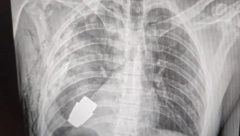

VOJNIKU IZ GRUDI IZVAĐENA NEEKSPLODIRANA GRANATA! Podvig hirurga